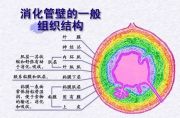

| 2021年7月26日 (一) 20:03 | 消化管壁的一般组织结构.jpg (文件) |  |

100 KB | Uploaded with SimpleBatchUpload | 2 |